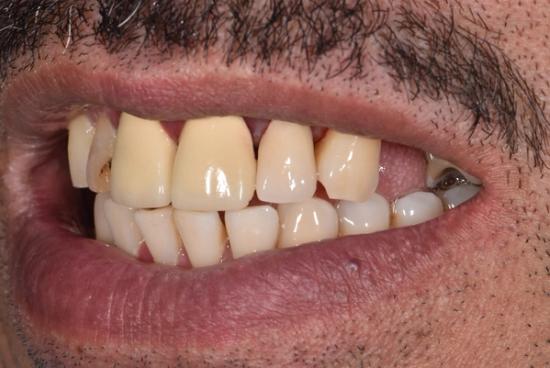

Before Photo